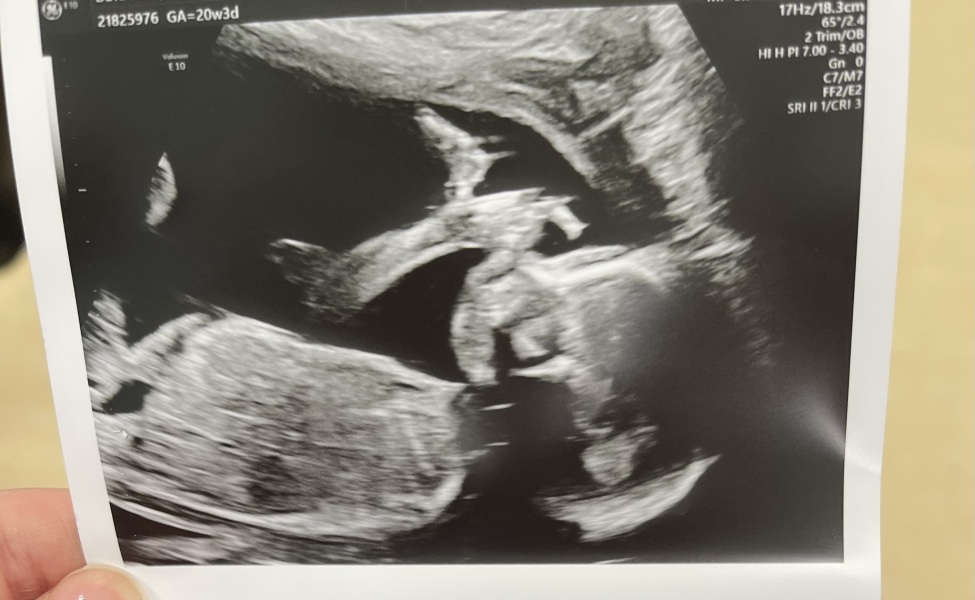

Morning ladies! We had our consultant scan this morning to follow up on baby boy’s kidneys. The news is as good as it can be given the circumstances - he’s likely to have reduced/no function in one kidney, but the other kidney looks healthy and there are no other issues. He’s also enormous 😂 leg length in the 98th centile and approx 70g heavier than average (but my husband is a 6’4 rugby player and I’m 5’10 so not such a surprise!)!

We also finally got a pic of him - they’d run out of printer paper at our 12 week scan and understandably it wasn’t a focus at our 20 week scan last week! ^^

So glad things went as well as can be giving the circumstances @mrsbgb and what a lovely scan picture 🩵

@mrsbgb lovely pic of your little chunky boy 🩵 so pleased today went well xx

Lovely scan @mrsbgb and so glad everything went well and your consultant isn't concerned.